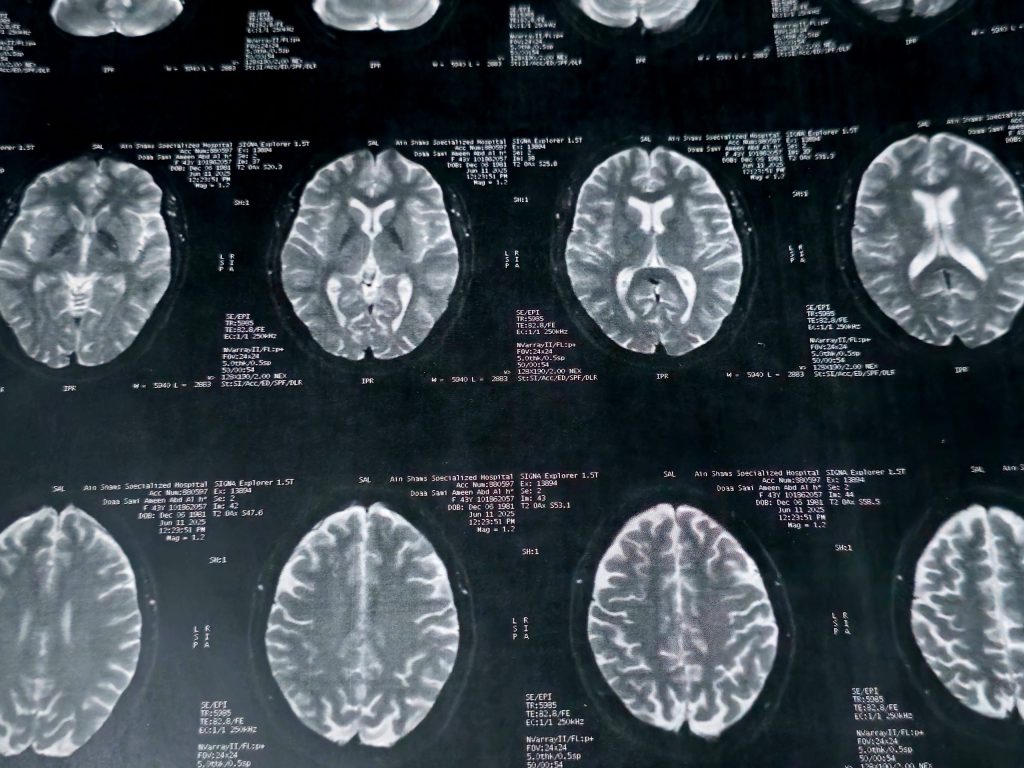

Depuis plus de 25 ans, des chercheurs de Northwestern Medicine, dans l’Illinois aux États-Unis, étudient un groupe de personnes âgées surnommées les SuperAgers afin de comprendre comment certains individus conservent une acuité mentale exceptionnelle à un âge avancé : à plus de 80 ans, leur mémoire rivalise avec celle de personnes de 50 ans[1].

Le plus « étonnant » (vous allez voir que tout est relatif), c’est que leur cerveau ne suit pas les règles « habituelles » du vieillissement.

Chez certains, les fameuses lésions associées à la maladie d’Alzheimer ne se forment tout simplement pas. Je le rappelle cependant à toutes fins utiles, ces lésions sont la marque de ce qu’on appelait autrefois la démence sénile ; vous voyez que la « normalité » est une notion toute relative dans ce contexte ; mais poursuivons.

Chez d’autres, ces lésions sont bien présentes… mais sans effet sur leurs capacités cognitives !

Les chercheurs commencent donc à décrypter ces deux stratégies naturelles que sont la résistance ou résilience.

Leur cerveau, notamment dans les zones liées aux émotions et à la motivation, semble même mieux préservé que celui d’individus plus jeunes.